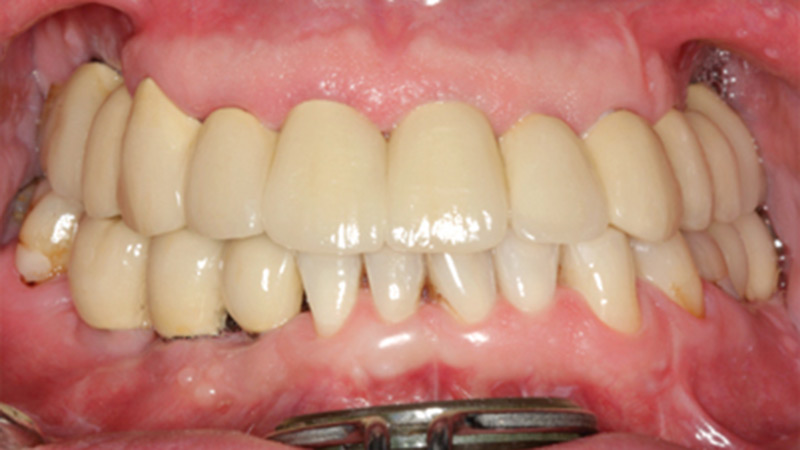

Transition From A Removable To A Fixed Implant-Supported Prosthesis: A Case Report

fixed implant

Abstract Incorporation of dental implants to support fixed and removable prostheses is an effective treatment modality for edentulous patients that provides enhanced patient function, comfort and overall quality of life in comparison to a conventional complete removable prosthesis. Both fixed and removable implant-supported prostheses for edentulous patients have specific indications although in many clinical situations … Read more